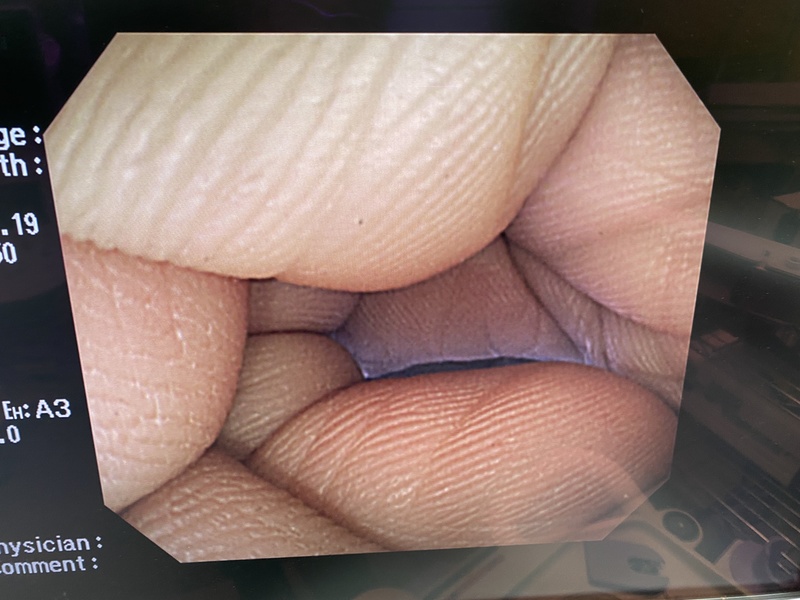

- detail Video Colonoscope / 17055 / PCF-Q260AI